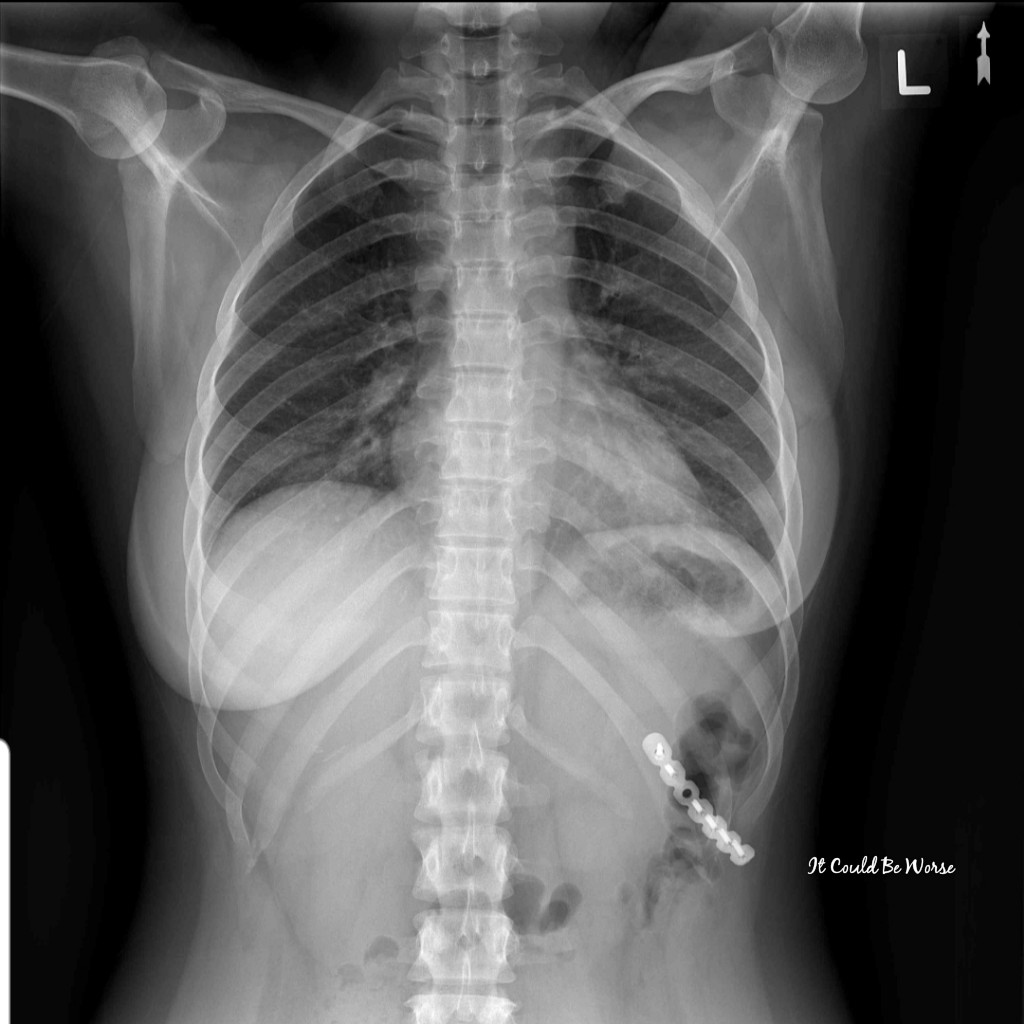

She ordered an x-ray but didn’t see anything wrong. I was given Tylenol with Codeine to help me not cough so much and help me sleep at night, with an NSAID cream to put on my painful ribs. Taking NSAID’s are a no-no for Crohn’s and IBD, so she knew not to prescribe me any and avoid tearing up my stomach. The same with antibiotics, she didn’t want to harm the healthy bacteria in my stomach either.

View X-ray #1